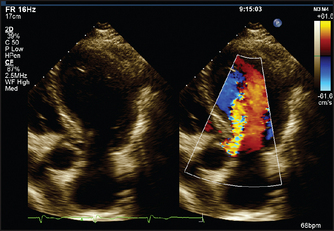

• In colour flow mapping, it is possible for echo machines to solve the Doppler equations for sectors of the two-dimensional scan in real time, assign a colour code depending on the direction and velocity of flow and superimpose this on the two-dimensional image. In this way, flow within the heart is visible in relation to the anatomy and abnormal jets of blood can be more easily detected (see Figure 8.18).

5. Aortic regurgitation. The valve may look thickened or occasionally a cusp may be seen to prolapse (see Figure 8.20). The aortic root size may be increased, especially if this is the cause of the aortic regurgitation. Left ventricular dilation is often present and the size of the ventricle may be used as an indication of severity. Doppler interrogation will show the regurgitant jet for a variable distance into the left ventricle.

Figure 8.20 Aortic regurgitation (From Baker T, Nikoli

G, O’Connor S, Practical cardiology, 2nd edn. Sydney: Churchill Livingstone, 2008, with permission.) Churchill Livingstone